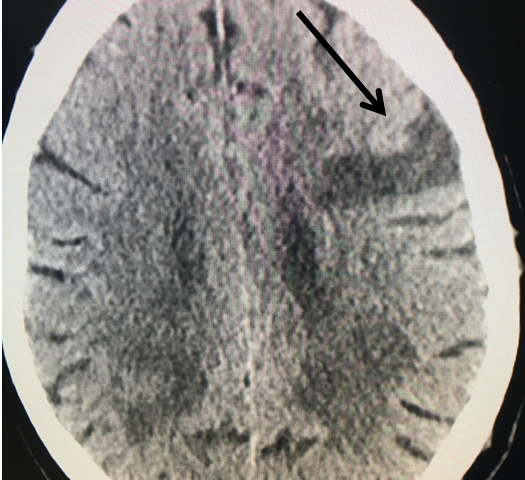

Figure 3.

Catheter angiography prior to angioplasty revealed critical stenosis (Figure 2). Angioplasty was therefore performed under local anesthesia with an embolic protection device deployed to catch any dislodged debris (Figure 3). After angioplasty, a stent was opened across the lesion to maintain long-term patency (Figure 4). Post-stent angiography showed smooth dilatation of the lesion. The patient’s aphasia continued to improve at his 6-week follow-up visit and duplex revealed no significant stenosis through the stent.